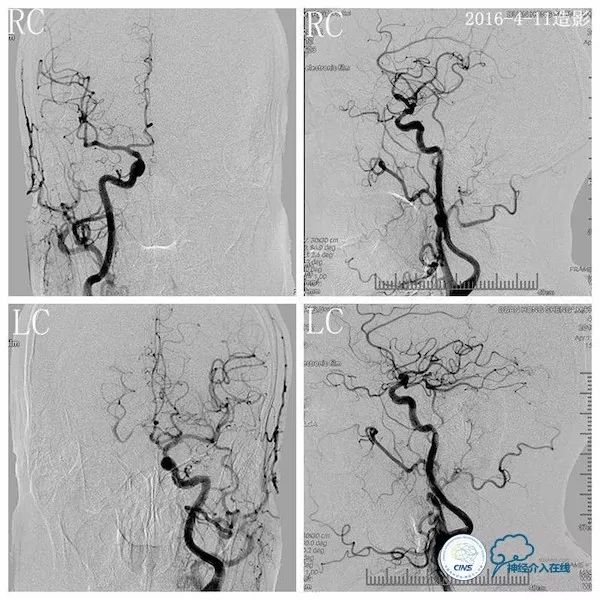

行头颅DSA示左椎动脉优势,左椎动脉V2段迂曲,基底动脉下段重度狭窄;左颈动脉造影见左后交通动脉开放,向双侧大脑后动脉及基底动脉远段代偿(2016-4-11,图3、4、5)。

图3

图4